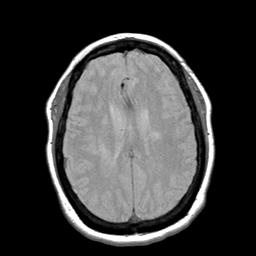

Cerebral hemorrhage, MR Study mr-pd -- Slice #15

[Home][Help][Clinical] Slice 15